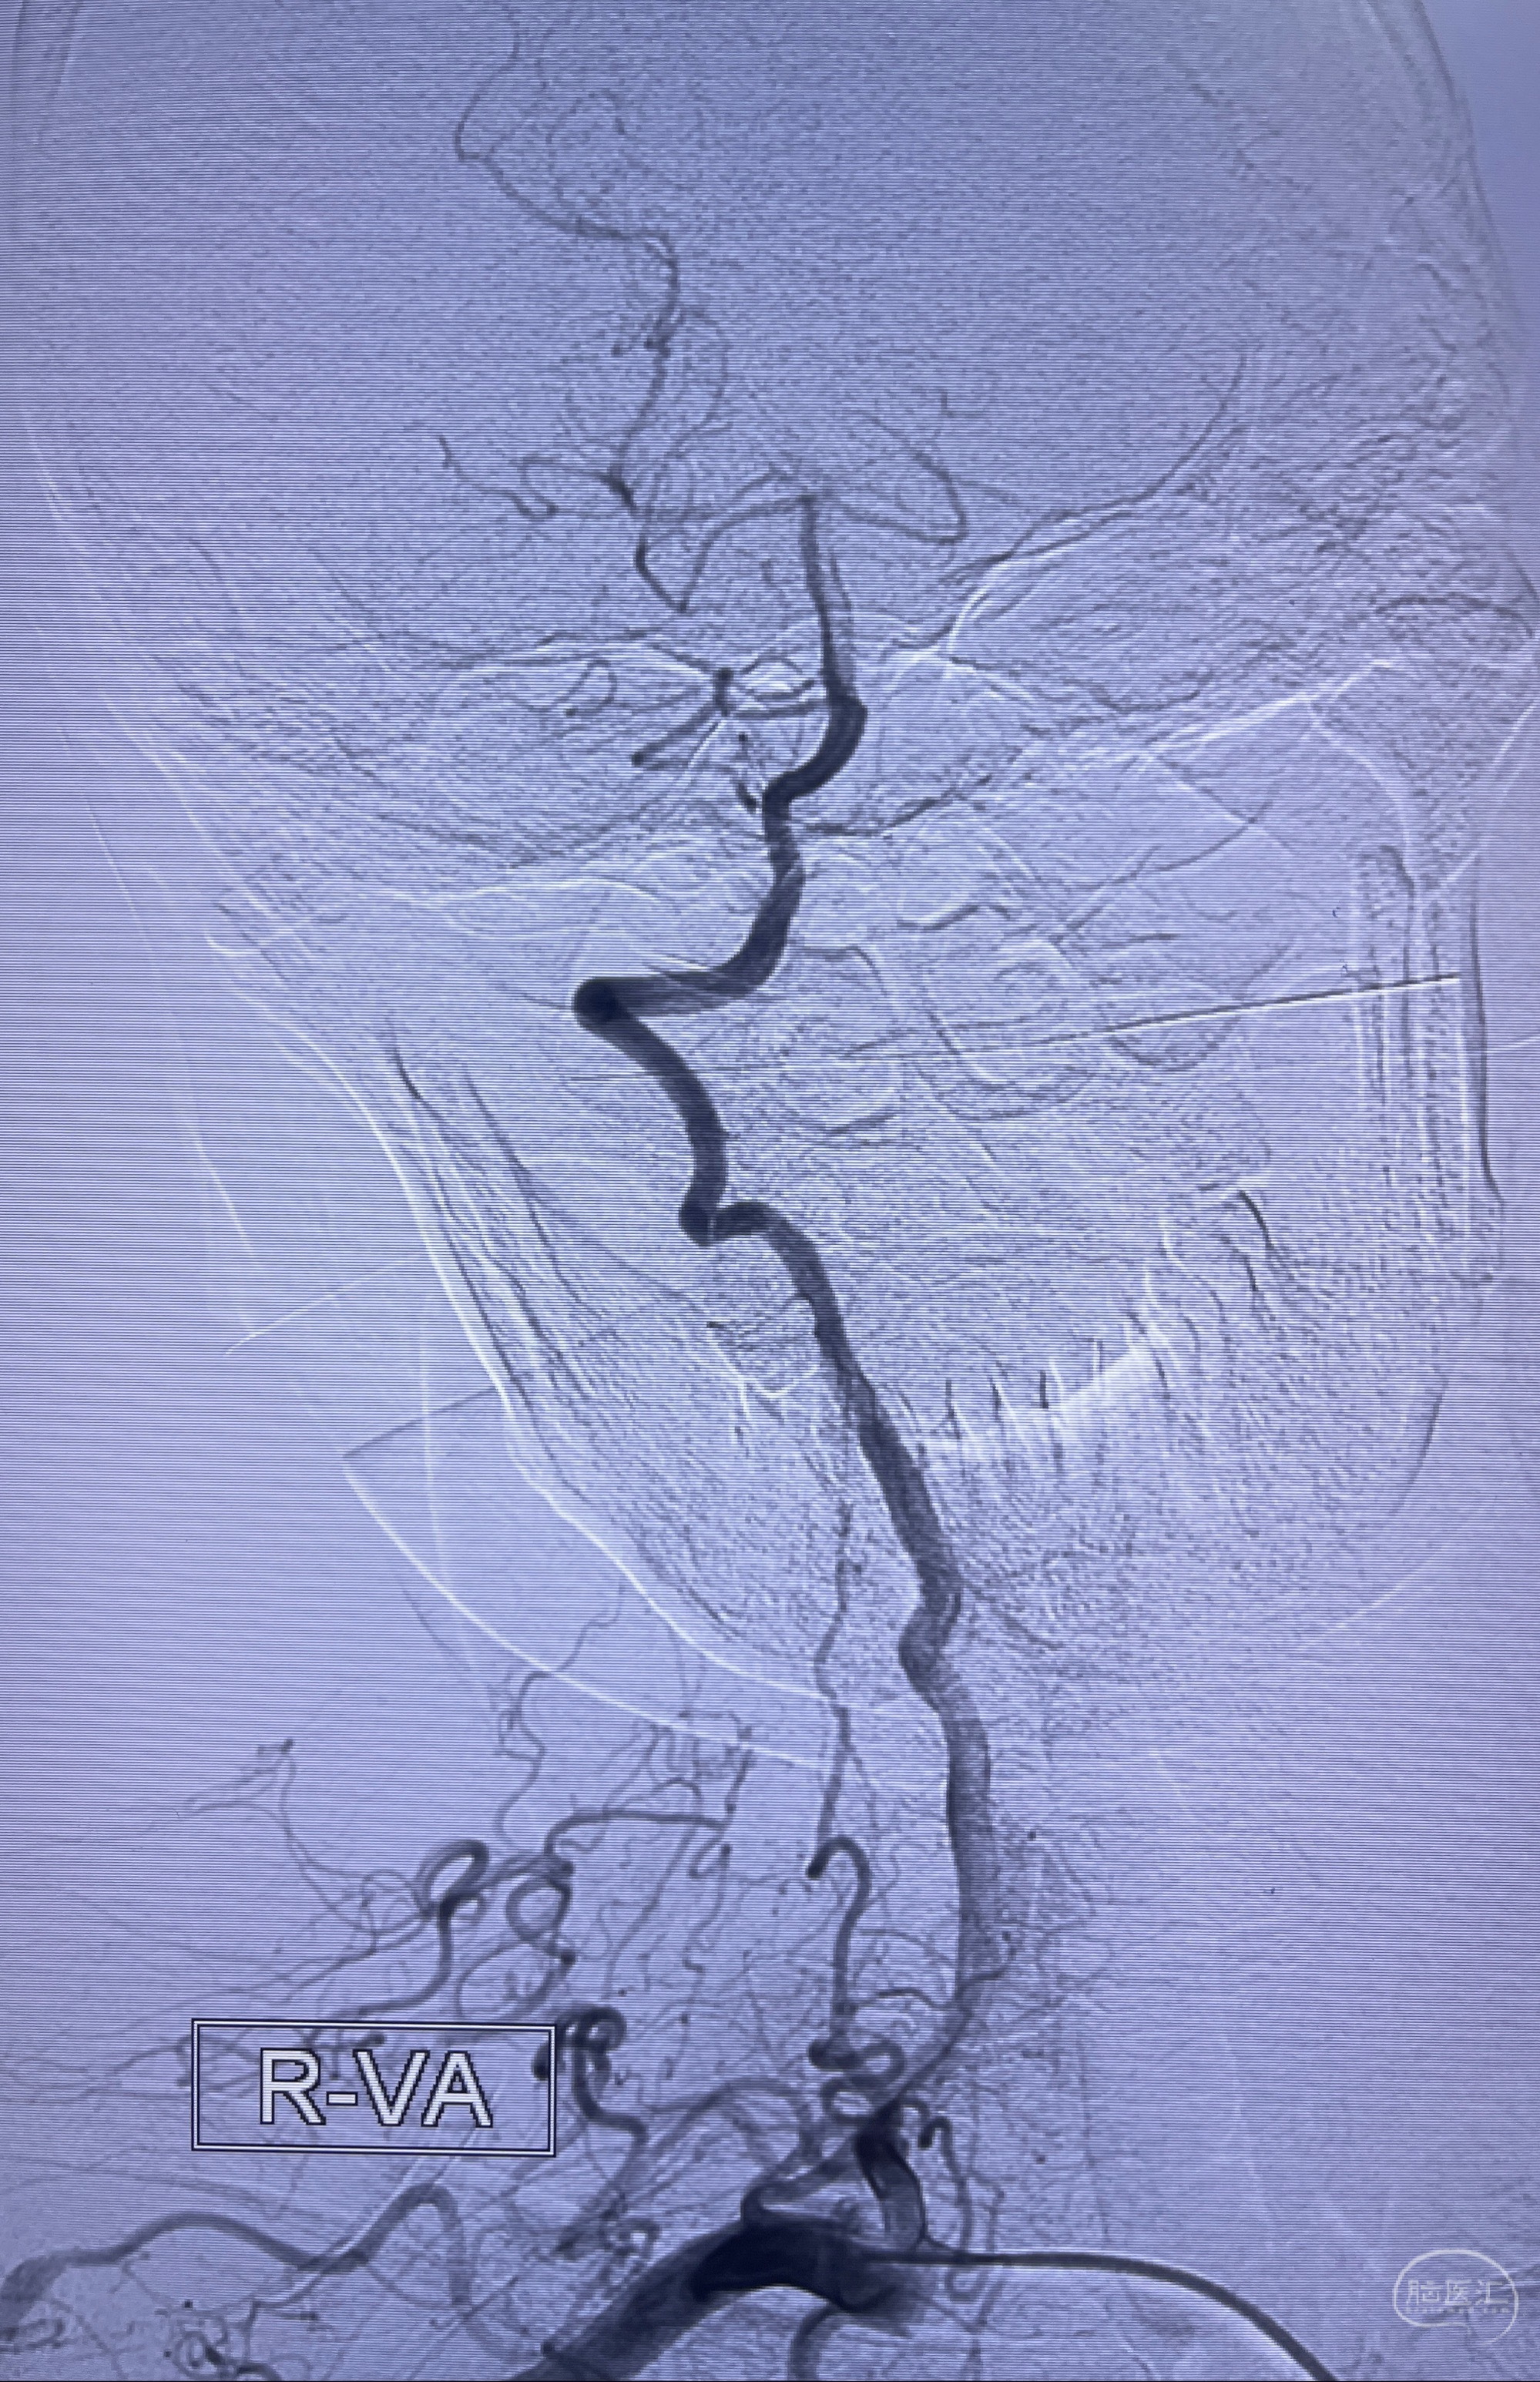

检查;2023-7-18 抚州市第一人民医院 头颈部CTA:左侧大脑前动脉A2段动脉瘤,左侧颈内动脉C4段轻度狭窄,右侧颈内动脉C6段中度狭窄

2023-08-23DSA:左侧前交通动脉瘤,左侧A3/4交界处多发动脉瘤